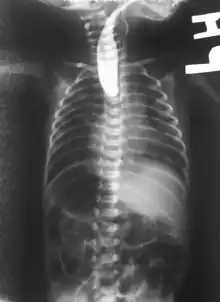

Plain x-ray with contrast in the upper esophagus above the atresia.

If any of the above signs/symptoms are noticed, a catheter is gently passed into the esophagus to check for resistance. If resistance is noted, other studies will be done to confirm the diagnosis. A catheter can be inserted and will show up as white on a regular x-ray film to demonstrate the blind pouch ending. Sometimes a small amount of barium (chalk-like liquid) is placed through the mouth to diagnose the problems. However, performing such an oral contrast study is not advised due to a risk of aspiration.[27]